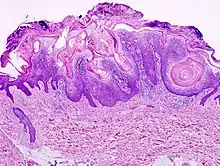

Visual diagnosis is made by the "stuck on" appearance, horny pearls or cysts embedded in the structure. Darkly pigmented lesions can be challenging to distinguish from nodular melanomas.[9] Furthermore, thin seborrheic keratoses on facial skin can be very difficult to differentiate from lentigo maligna even with dermatoscopy. Clinically, epidermal nevi are similar to seborrheic keratoses in appearance. Epidermal nevi are usually present at or near birth. Condylomas and warts can clinically resemble seborrheic keratoses, and dermatoscopy can be helpful. On the penis and genital skin, condylomas and seborrheic keratoses can be difficult to differentiate, even on biopsy.

A study examining over 4000 biopsied skin lesions identified as seborrheic keratoses showed 3.1% were malignancies. Two-thirds of those were squamous cell carcinoma.[10] To date, the gold standard in the diagnosis of seborrheic keratosis is represented by the histolopathologic analysis of a skin biopsy.[11]